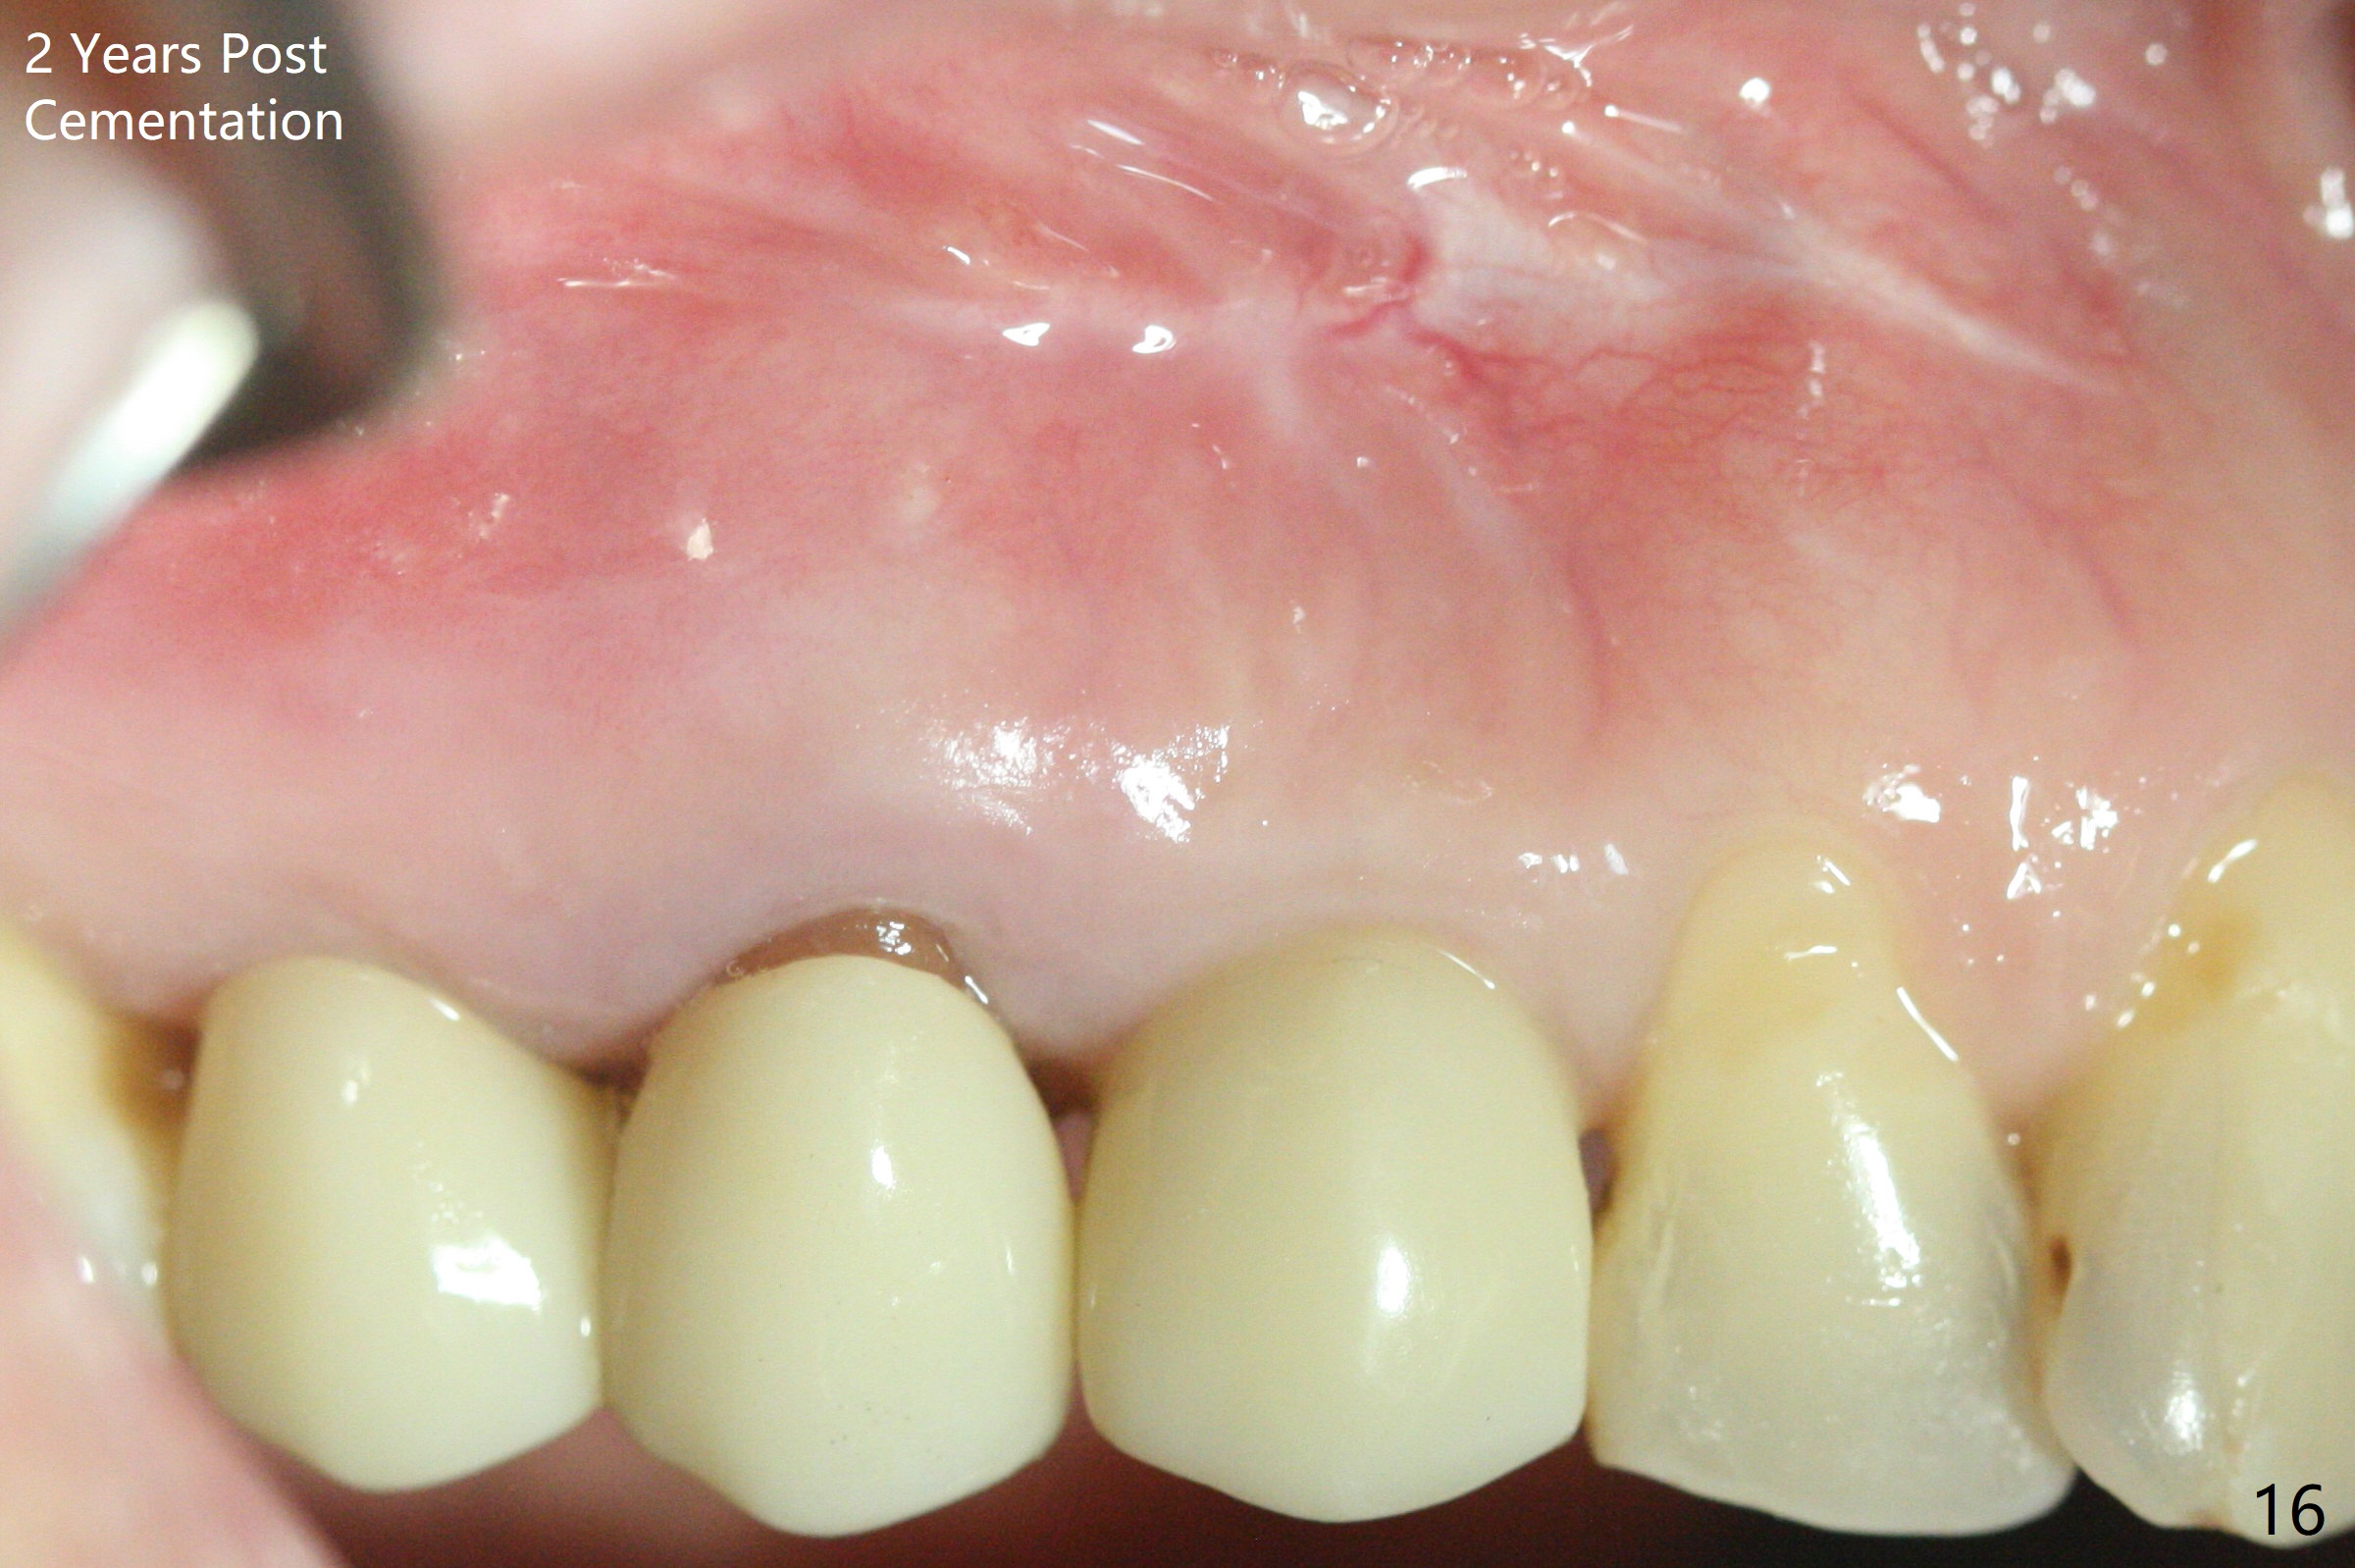

Osteotomy starts with guide and 2.2 mm drill for initial 3.5 mm palatal. A semilunar incision is made buccal to remove the impacted canine (#6 by sectioning). With direct vision buccal and palatal, the final osteotomy is finished free hand with 1.2 and 1.5 mm drills. Initially buccal perforation occurs, the osteotomy route is corrected later (Fig.1). When a 2.5x15 mm 1-piece implant is being placed, it perforates into the buccal concavity again. After redirection, the trajectory seems to be acceptable (Fig.2: CT coronal section). Three coronal implant threads are exposed partially palatal (Fig.3: CT 3-D palatal view). The implant is then turned 2-3 times with insertion torque reaching 40 Ncm. The incision is closed with suture following Osteogen plug placed in the most coronal portion of the socket (Fig.4 P) and allograft (*) in the remaining socket around the apical portion of the implant as well as palatal. The incision does not heal 1 month postop (Fig.5). PRF membrane will be placed next visit. Next visit the wound in fact is healing (Fig.6). PRF is unnecessary. The patient will return for impression 3 months postop. To be cosmetically pleasing, prepare local anesthetic and Laser for gingivectomy (Fig.7 red curved line). There is no bone loss around the implant 3.5 months postop (Fig.8). With topical, minor gingivectomy with laser creates papillae mesial and distal to the implant (Fig.9, 10 (incisal view)). After reline, there is appearance of a canine (Fig.11). The patient returns for impression 5 months postop; there is bone around the apex of the implant (Fig.12 *). The hard and soft tissues remain healthy when final restoration is delivered (Fig.13,14). The buccal plate reforms and #6 socket heals 12 months postop (6 months post cementation, Fig.15). The gingiva remains healthy at #4-6 nearly 2 years post cementation (Fig.16).